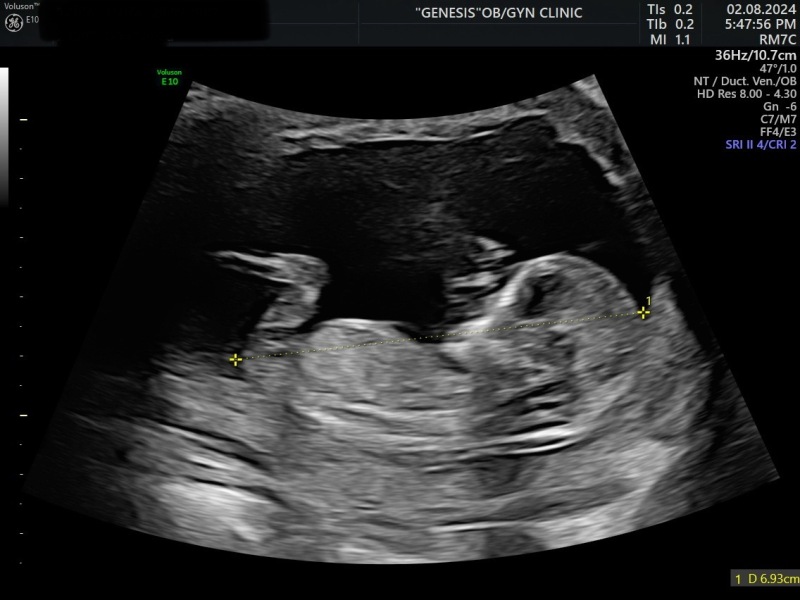

Felicity20 · 04/08/2024 10:03

Hello, got boy based on nub theory on week 12, is there a chance to have a girl? Has anyone such an experience? Thanks in advance!

Nub theory prediction wrong?